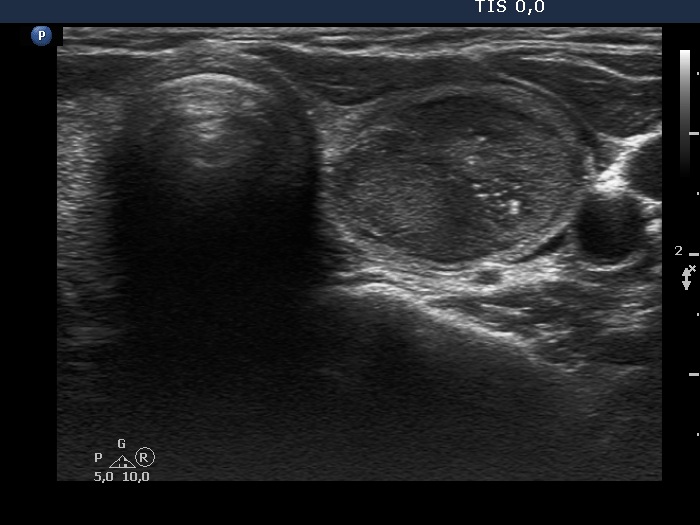

Hashimoto's thyroiditis with several cystic areas but without any nodules (histological diagnosis) - case 1365

There is no doubt of the origin of the hyperechogenic figure in the cystic lesion, this is a typical comet-tail artifact.

At first sight the interpretation of these figures seems to be difficult. However, this lesion is in the same patient whose other lesion is presented in the left images. It is reasonable to conclude that similarly bright figures within lesions presenting an identical echo pattern have the same origin.